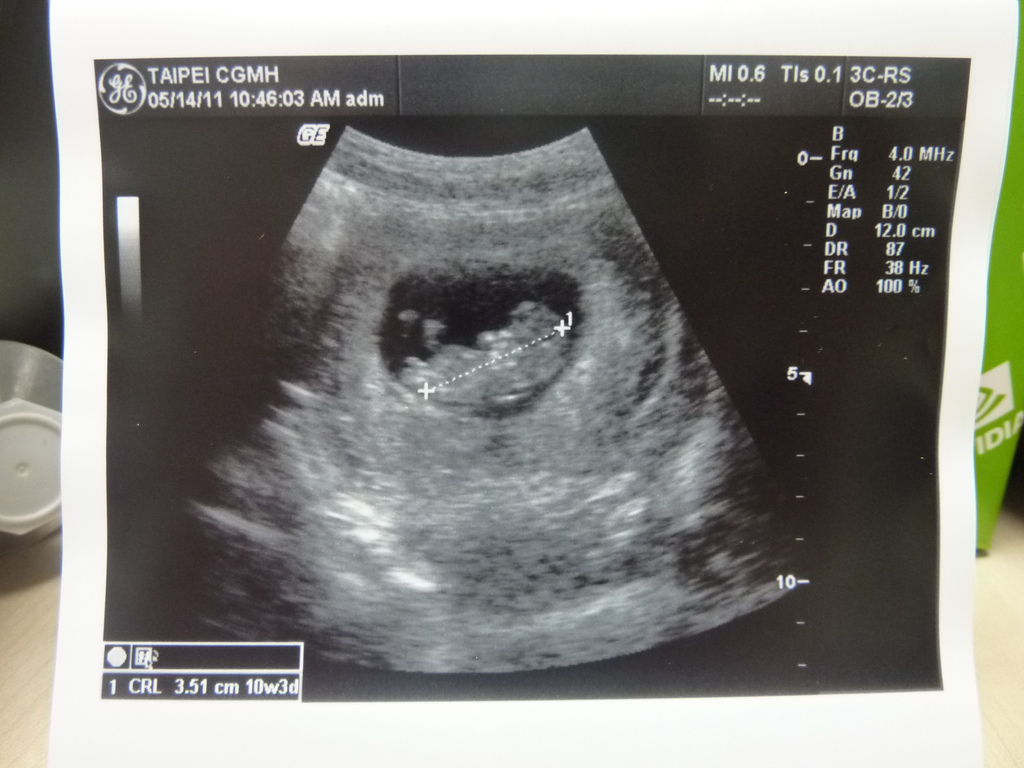

然後開始照超音波.哇~看到頭與身體及小手腳的那剎那還是那麼一點感動

醫生也都做基本簡單的說明-胎兒大小.心跳.羊水等等..

就決定換到長庚了!!! 回家還看到夾著三張超音波的寫真照真是揪感心呀~